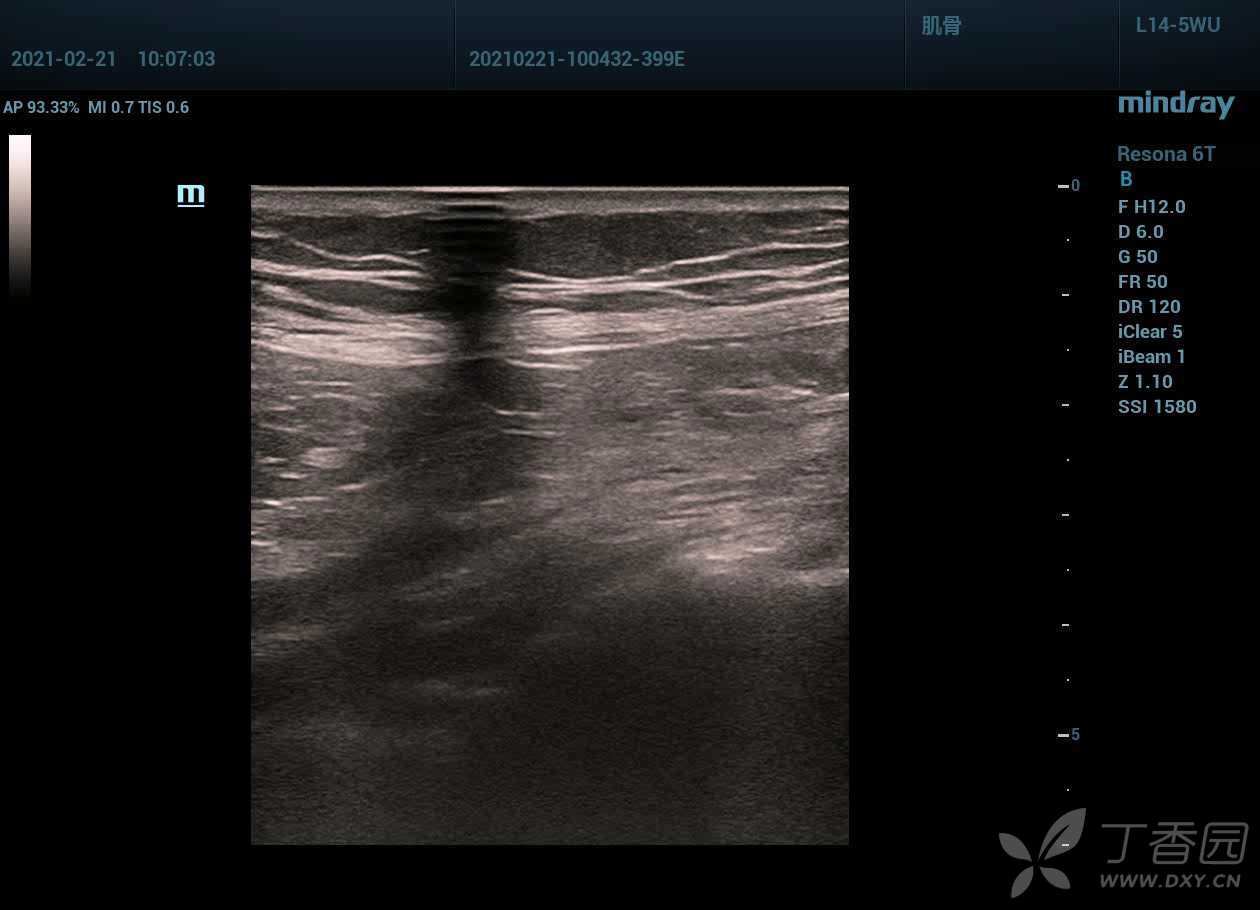

容易踩坑哦,你能爬上来吗?右下腹痛阑尾彩超检查。